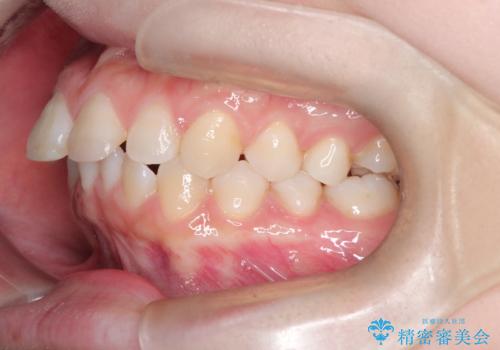

- 前歯のデコボコ(叢生)を気にされてご来院されました。精密な検査の結果、歯が並ぶスペースが不足していることが判明。患者様のご希望から、透明で目立ちにくいインビザライン(マウスピース矯正)による治療計画を立案しました。抜歯を避け、奥歯全体を奥へ動かす遠心移動という方法でスペースを確保し、前歯の叢生を解消することを目指します。

今回の矯正治療では、透明なマウスピース型の装置インビザラインを使用しました。この装置は取り外し可能で、日常生活で目立ちません。治療は、緻密に計算された計画に基づき、段階的に作製されたマウスピースを交換していくことで、奥歯から順に全体を後方へ移動させる遠心移動を実施。これにより、前歯を並べるための十分なスペースが確保され、デコボコが解消されました。抜歯することなく、機能的にも審美的にも整った美しい歯並びを獲得していただけました。